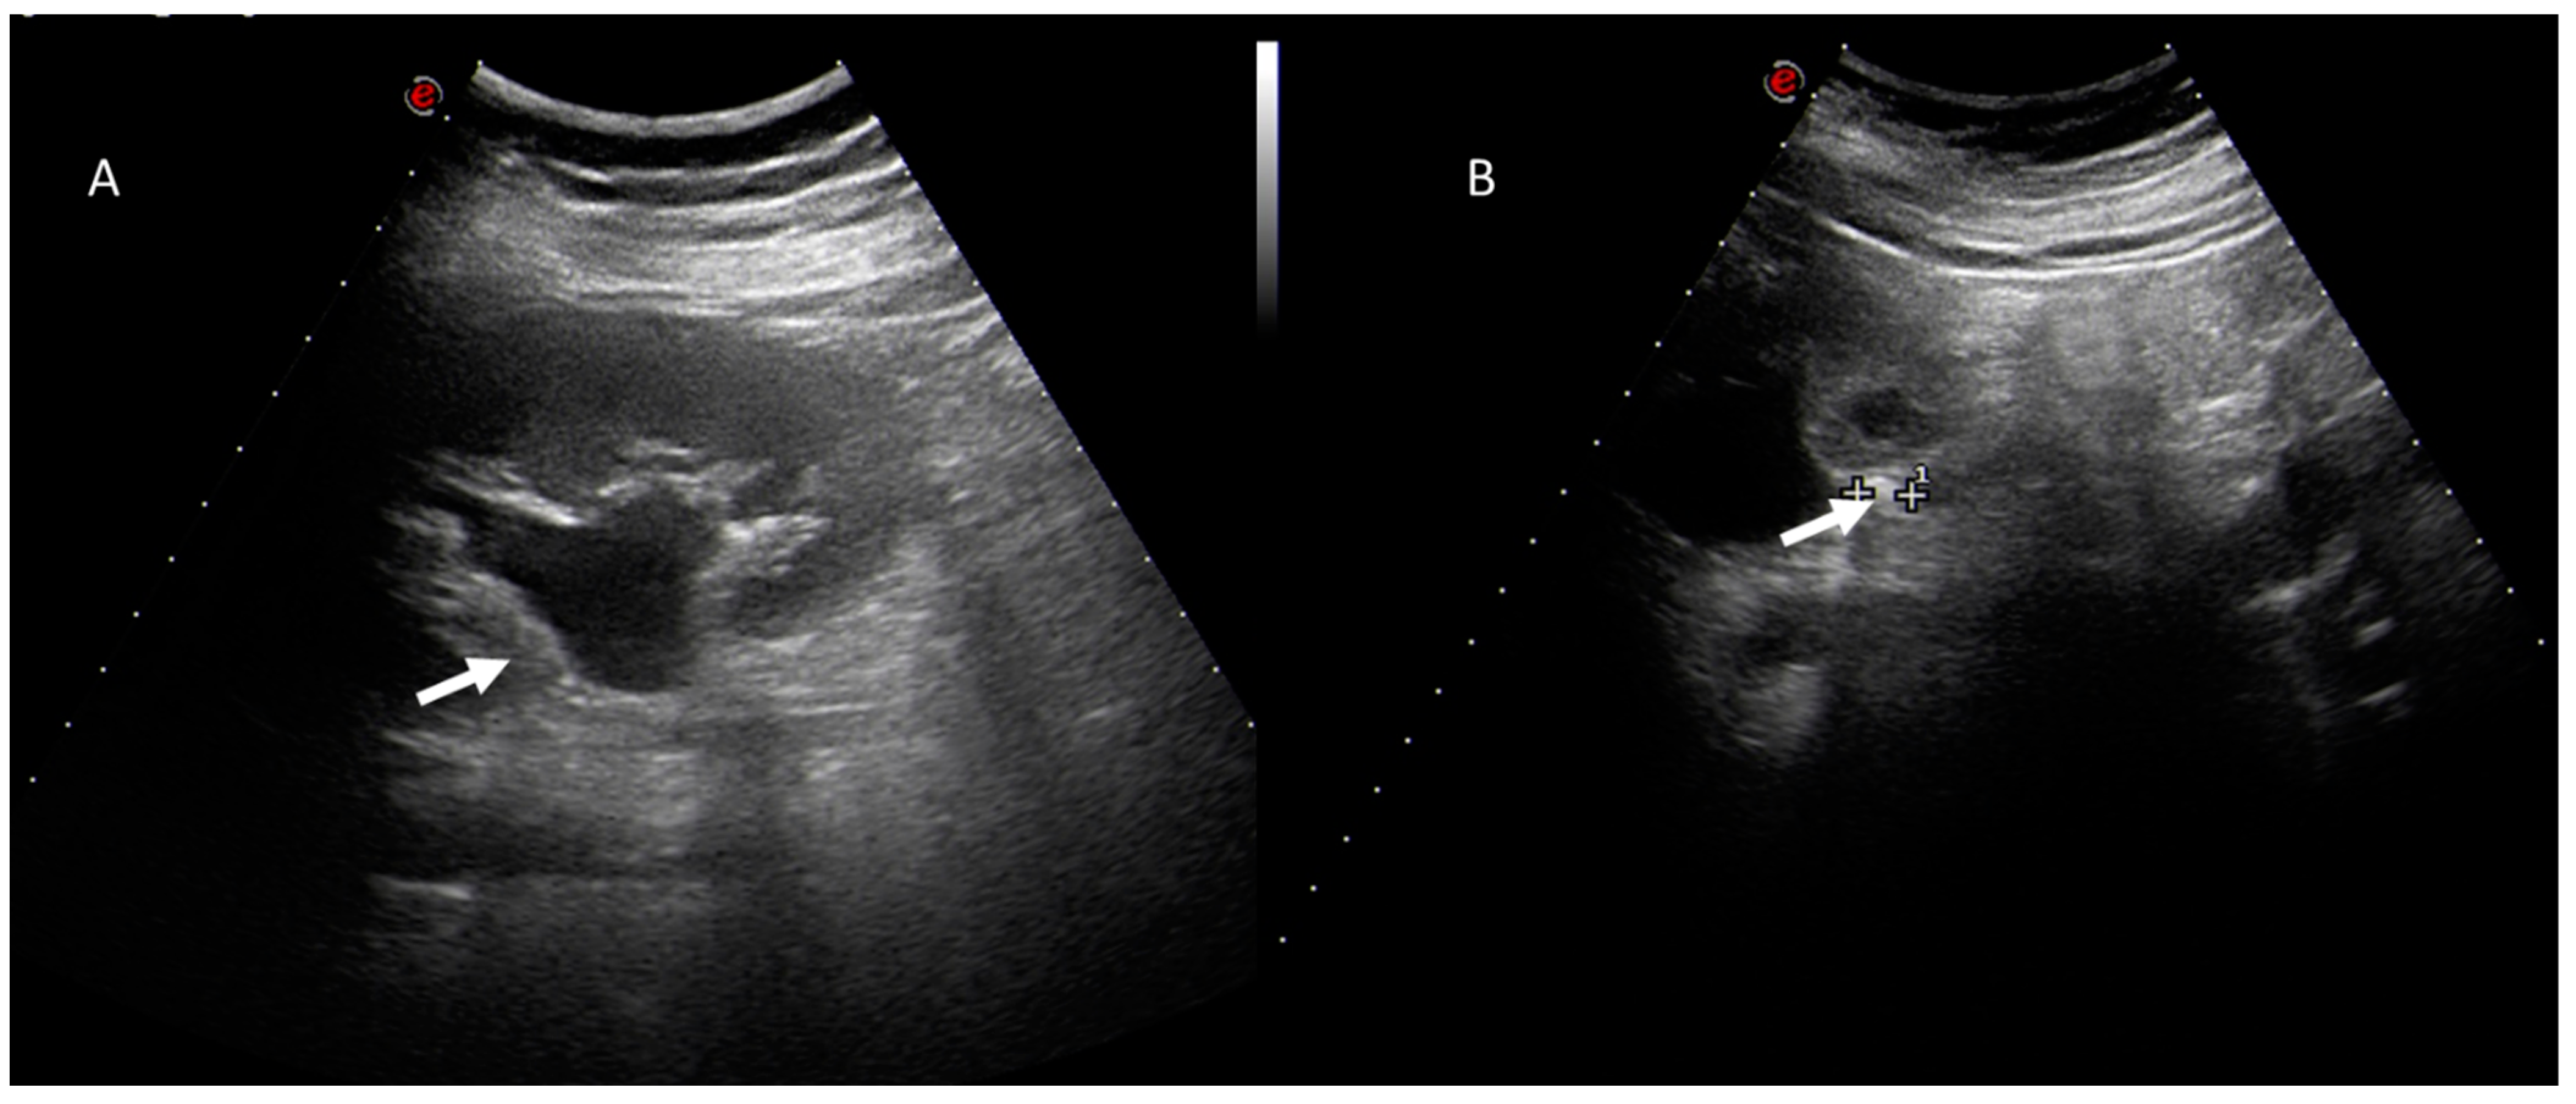

5. Acute Appendicitis

6. Biliary Tract and Pancreatic Diseases